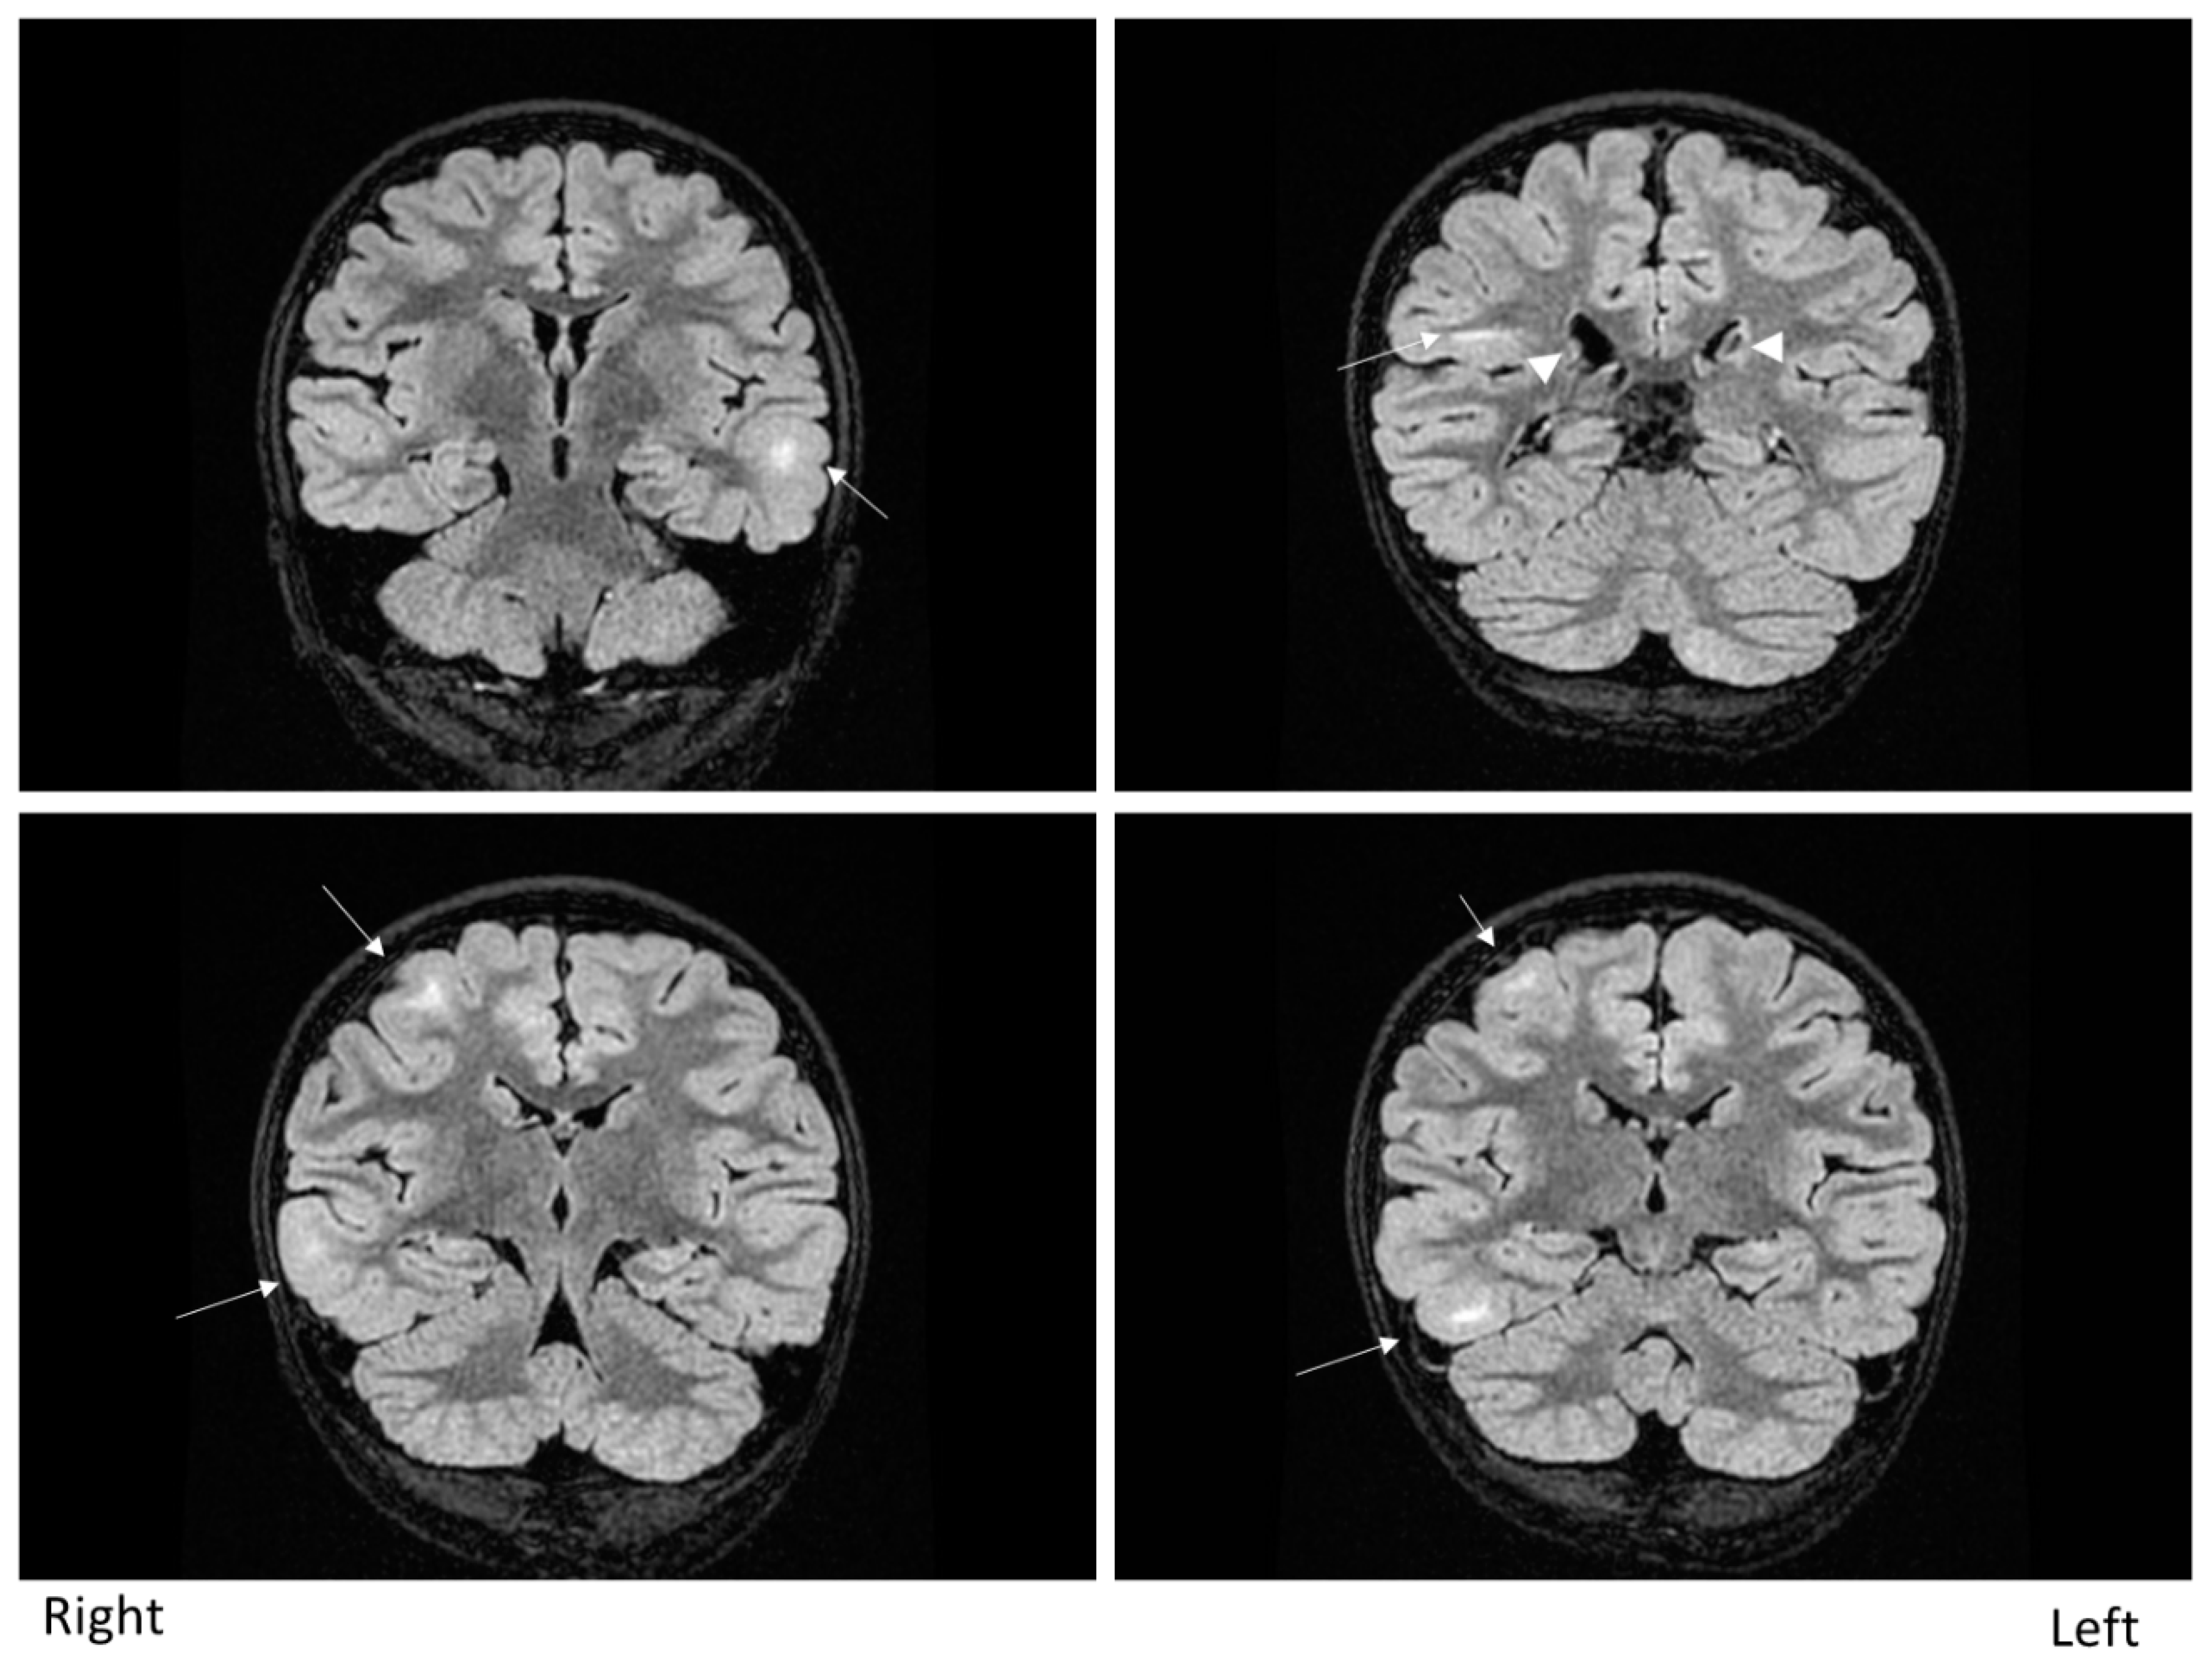

The patient was a nine-year-old girl with epilepsy secondary to TSC. She started experiencing focal-onset impaired awareness seizures from six months of age. The seizure frequency was weekly. Brain magnetic resonance imaging showed multiple cortical and subcortical tubers (Figure 1). Electroencephalography (EEG) showed frequent epileptiform discharges over bilateral hemispheres independently, comprising multiple independent spike foci. Ictal events captured by long-term video-EEG showed stereotypical seizures arising from the right frontotemporal area. The patient, therefore, underwent invasive monitoring followed by a right anterior temporal lobectomy with amygdalohippocampectomy. In addition to epilepsy secondary to TSC, this patient also had juvenile facial angiofibroma, hypopigmented macules (“ash leaf” patches) on the limbs, shagreen patches on the back and polycystic kidneys with no angiomyolipomas. No abnormalities were apparent on cardiological, dental and ophthalmological studies. Genetically, a TSC2 missense mutation was confirmed.

Figure 1. Brain magnetic resonance imaging (MRI). Fluid-attenuated inversion-recovery (FLAIR) MRI shows multiple cortical and subcortical tubers (arrows). Subependymal nodules are indicated by arrows.